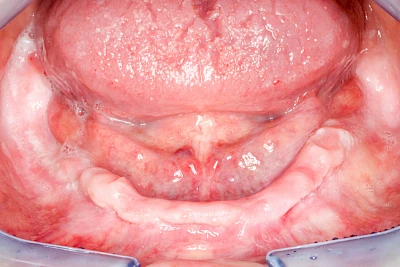

Überbeine im Bereich der Kiefer sind gar nicht so selten. Häufiger im Bereich der Seitenzähne unterhalb des Zahnfleisches, aber auch in der Mitte vom Gaumen. Überbeine haben in dem Sinne keinen Krankheitswert, müssen also nicht operativ entfernt werden, wenn diese nicht stören. Überbeine können ein Anzeichen für Knirschen und Pressen sein.

In seltenen Fällen schwindet nur der Knochen, aber nicht die bedeckenden Schleimhäute. In diesen Fällen spricht man von einem sogenannten "Schlotterkamm".